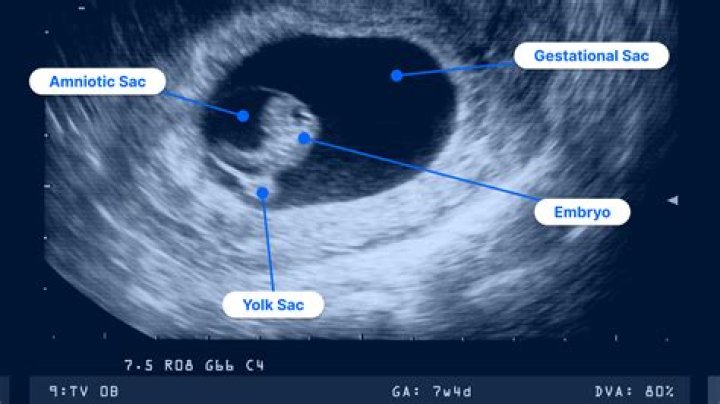

Generally, from 6 ½ -7 weeks is the time when a heartbeat can be detected and viability can be assessed. A normal heartbeat at 6-7 weeks would be 90-110 b...